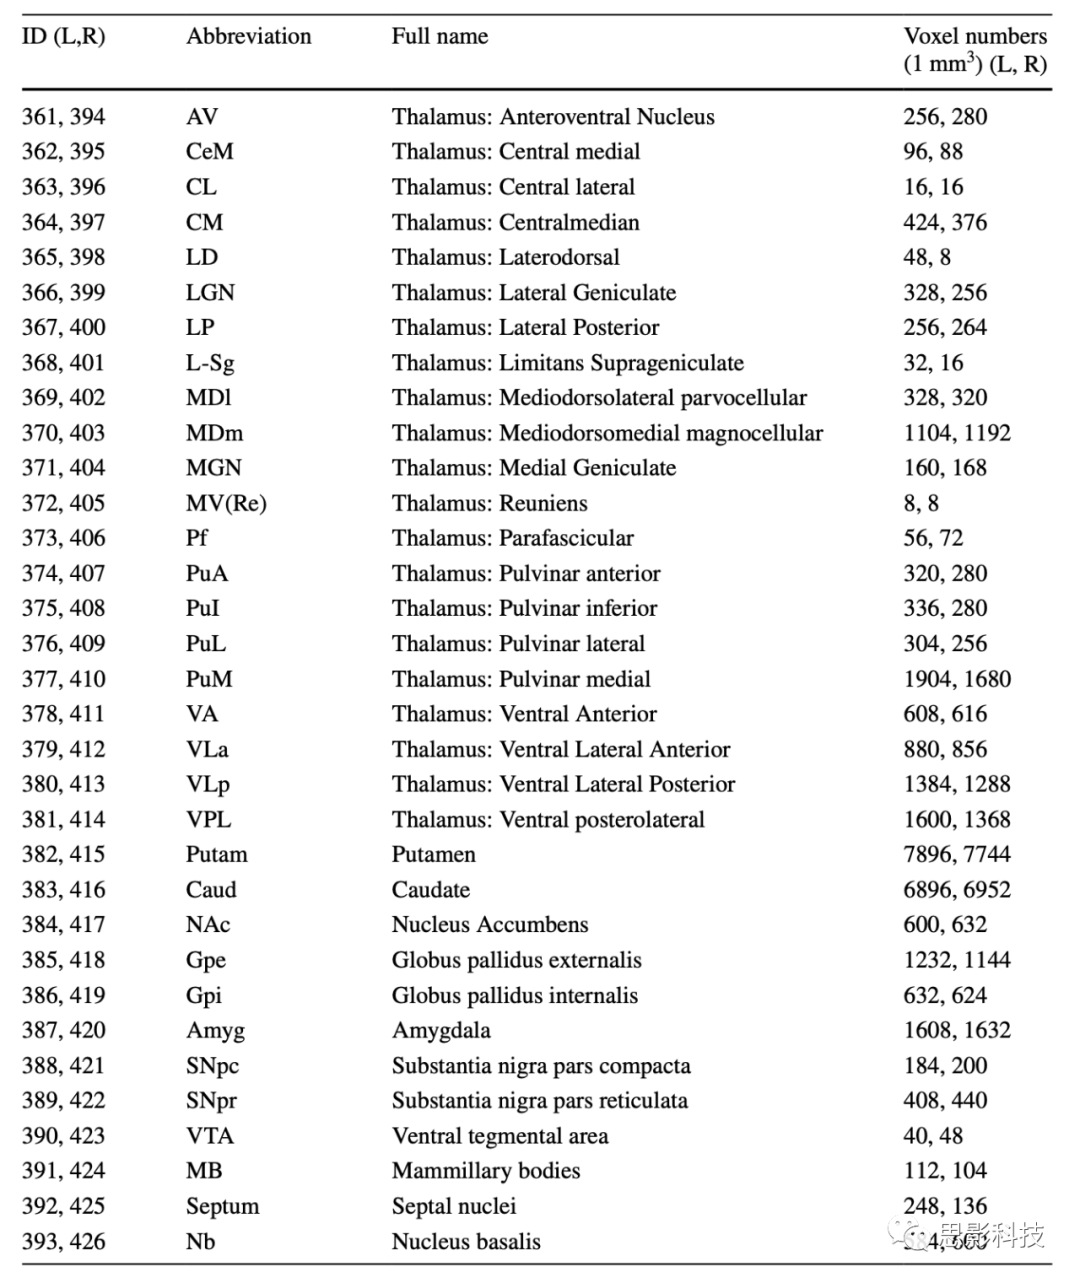

这里描述的扩展图集结合了以下区域:HCP 的多模态分割 (v1.0),每个半球由 180 个区域组成(Glasser 等人,2016a); 21个丘脑核; 以及其他12个皮质下区域,包括杏仁核、壳核、尾状核、伏隔核、苍白球外部、苍白球内部、黑质致密部、黑质网状部、中脑腹侧被盖区、乳头体、隔核和基底核 。 皮层下区域列于表 2 中,也显示于图 1 中。

表2 图谱中皮下区域的列表

在修改后的HCP-MMP1图谱中增加了总共66个新的皮层下区域(每个半球33个)。提供了新添加的皮下细分的列表(表2)。HCPex图谱中的新皮下区域从ID 361到426(左:361–393,右:394–426)。新的皮下区域包括21个丘脑核(361–381,394–414),壳核(382,415),尾状核(383,416),伏隔核(384,417),苍白球外侧部/内侧部(385–386,418–419),杏仁核(387,420),黑质致密/网状部(388–389,421–422),中脑腹侧被盖区(390,423),以及乳头体(391,424),还有胆碱能核:隔核(392,425)和基底核(393,426)。所有的皮层和皮层下区域都配准到了使用ICBM 2009c非对称模板定义的标准MNI空间中。皮层下区域的定义在接下来的部分中描述。

FreeSurfer模块将丘脑分割为每个半球25个不同的核团。然而,一些丘脑核团非常小,以至于它们在空间上可能不准确或不适用于进一步的基于感兴趣区(ROI)的分析。因此,我们通过根据它们的原始定义或最近邻居合并小核团来减少丘脑核团的数量。在HCPex图谱中定义的结果产生的21个丘脑核团的详细描述显示在表1中。

Iglesias et al.(2018)提供的丘脑细分使得HCPex图谱中每个半球包括21个丘脑核团,并因此被优先使用,而不是Tian et al.(2020)提供的只有8个丘脑核团的图谱。从Iglesias et al.(2018)采用的丘脑细分已通过使用基于人脑组织学的Krauth et al.(2010)图谱进行了验证,如补充材料中所描述的(图S1)。作为进一步的验证,采用白质消除MP-RAGE成像技术,将丘脑分割为12个核团的Thalamus Optimized Multi Atlas Segmentation(THOMAS)图谱中的人类丘脑核团也显示在图S1中(Su et al. 2019)。